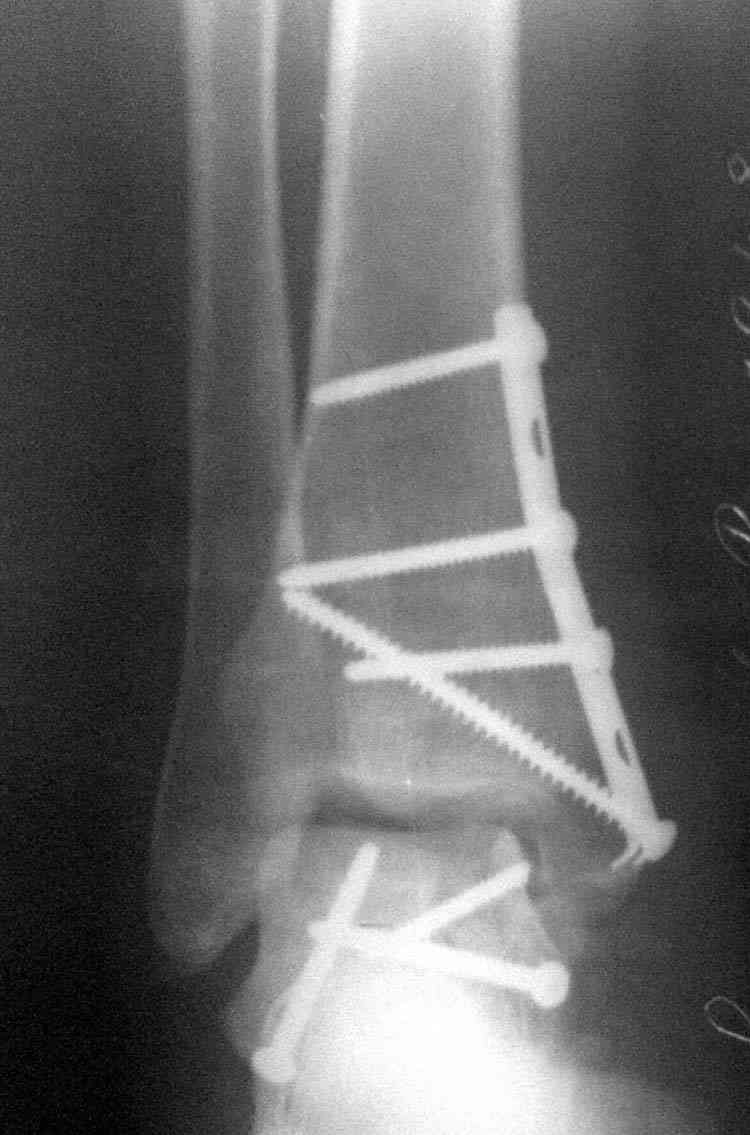

Случай с множественным оскольчатым переломом тарана оперированный из двойного доступа.

Через 14 мес.: